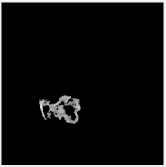

| Query Images |

|

| Segmented Images |